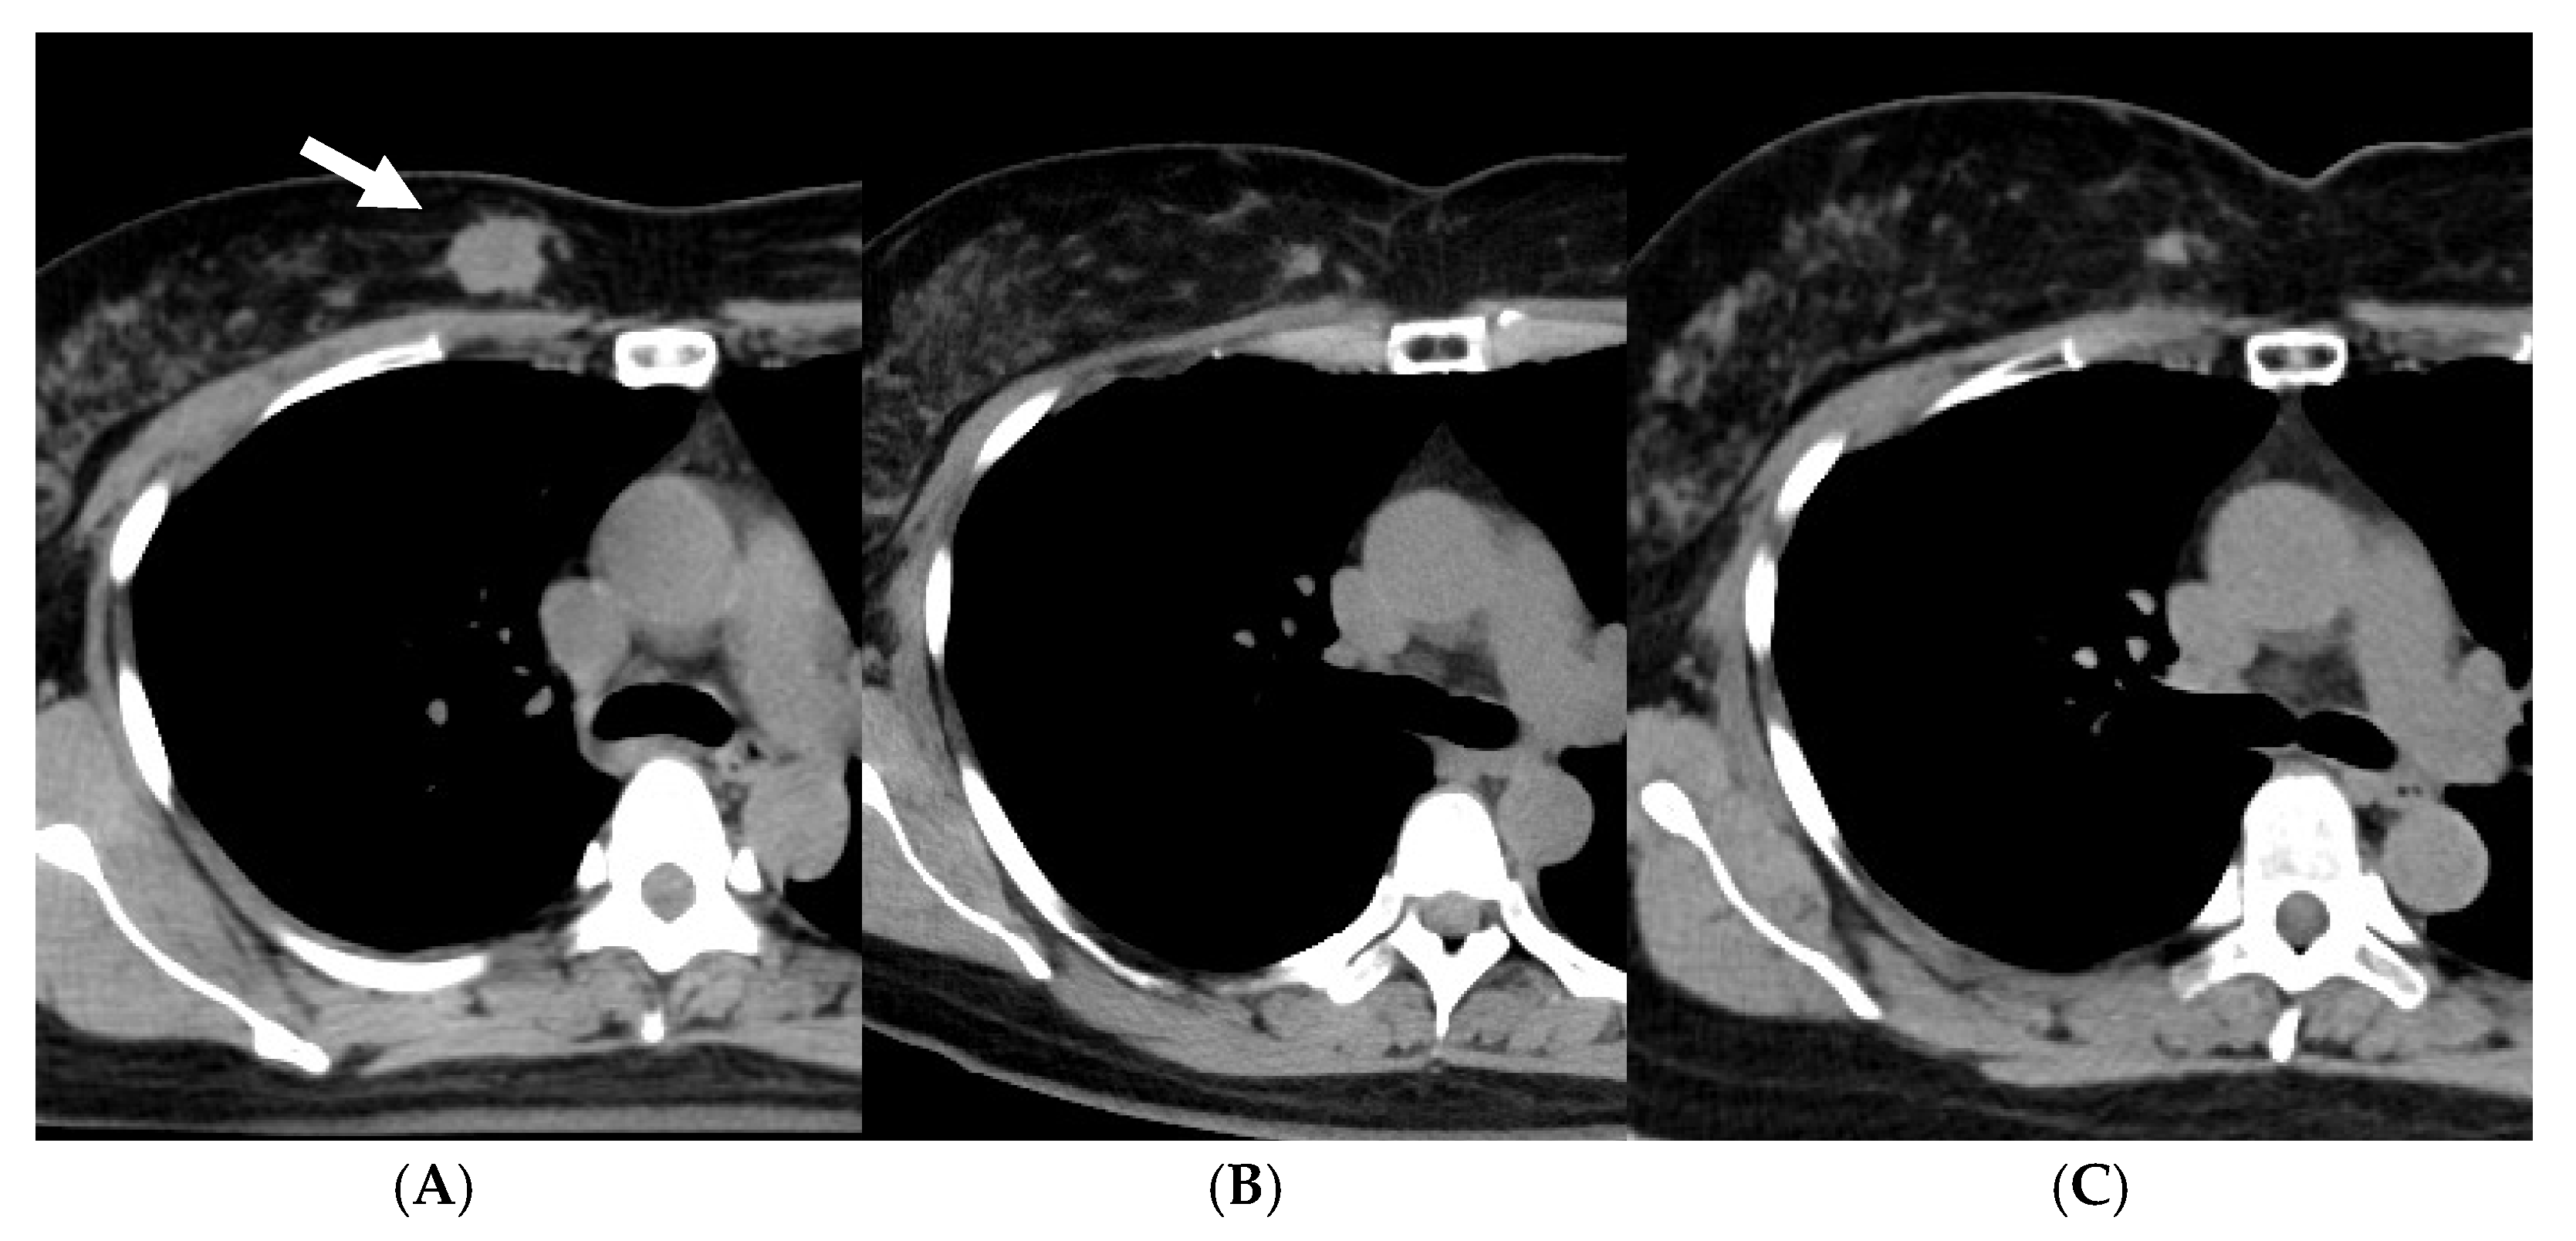

- Shibamoto, Y.; Takano, S.; Iida, M.; Urano, M.; Ohta, K.; Oguri, M.; Murai, T. Definitive radiotherapy with stereotactic or IMRT boost with or without radiosensitization strategy for operable breast cancer patients who refuse surgery. J. Radiat. Res. 2022, 63, 849–855. [Google Scholar] [CrossRef]